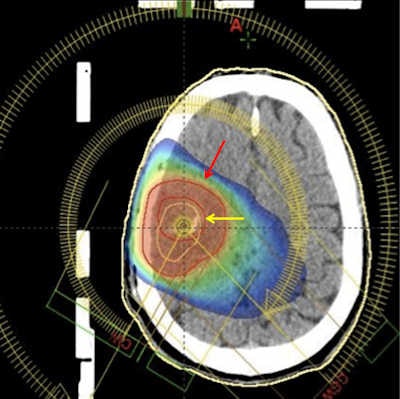

Radiation treatment planning of a brain tumor. Adding 11C-methionine PET increases the tumor volume (red arrow) when compared to the blood brain disruption as imaged by gadolinium-enhanced MRI (yellow arrow).In the next five years, we will likely see another technetium shortage. Although dedicated investments and new production techniques are going to reduce the impact of the next molybdenum production crisis, the global economic crisis will have a negative impact on the availability of the widely used radionuclide for single-photon molecular imaging. The reduced availability of funding for renovation or construction of production facilities, the increased costs of transportation, and the reduction in research funding will contribute to the difficulties in keeping the availability of technetium at the requested level for worldwide supplies. This is going to be another driving force to the use of PET techniques, as an alternative to single-photon imaging.